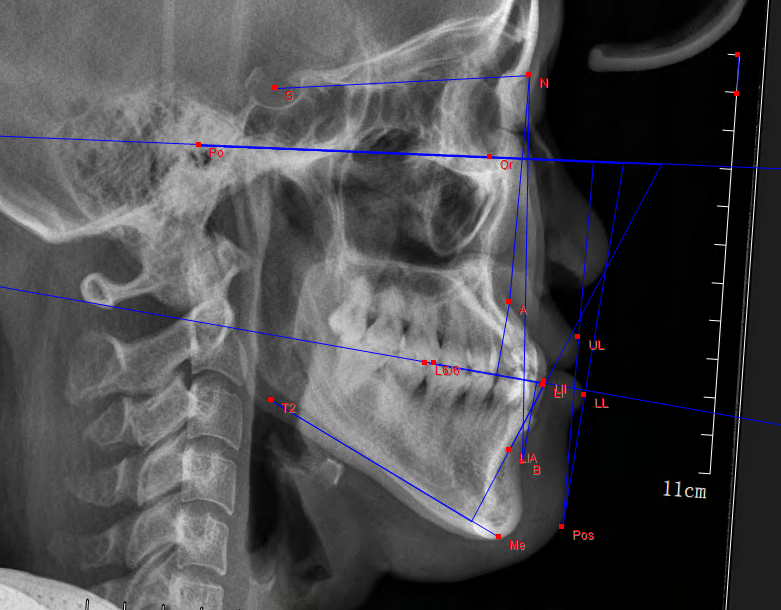

一、X线头型测量片

可以让医生了解到牙颌颅面的发育情况,将诊断从表面观察,深入到对整个骨骼的判断,做到精准定位、测量、制定矫治计划。